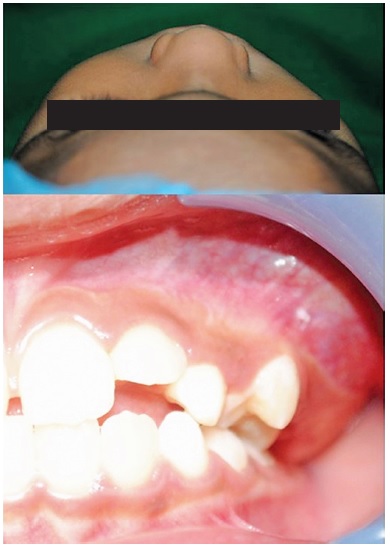

A seven-year-old male was referred for consult at the oral & maxillofacial surgery & implantology section of the hospital due to a large asymptomatic left maxillary mass resulting to a noticeable facial asymmetry. Clinical examination showed a solitary bony hard swelling on the left posterior maxilla exhibiting buccal and palatal expansion. Tooth mobility of the left premolars and absent permanent molar are likewise noted (Figure 1). CT scan showed an enlarging mass on the left posterior maxilla exhibiting an amorphous ovoid opacity surrounded by a defined radiolucent border overlying the crown of a permanent molar displacing the maxillary sinus floor without perforating it. (Figure 2) Based on the initial diagnostics considered impressions where ameloblastic fibro-odontoma and calcifying epithelial odontogenic tumor. Patient was admitted, prepared, once cleared underwent surgical enucleation of the mass under GETA via an intra-oral Lefort 1 incision, the mass was then submitted for histopathologic examination. 11 months after the operation (Figure 3), both clinical and radiographic findings show no sign of recurrence.

Figure 1. Clinical appearance. Mass producing facial asymmetry on left side of the patient, intra oral finding showing an evident bony hard mass on the posterior region of the left maxilla with noticeable altered eruption pattern of the left permanent molars.

Figure 3. Clinical appearance 11 months post-operatively showing improvement in facial symmetry and defect on the operative site with no clinical sign of recurrence.